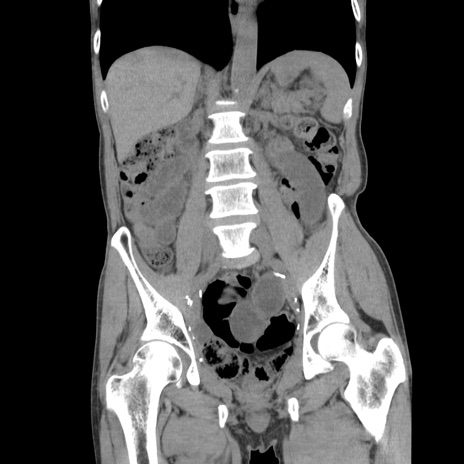

症例11(冠状断像)

【症例】 60歳代男性

【主訴】 下腹部痛

【現病歴】 本日夜中より下腹部痛の症状認め、受診。

【既往歴】 膀胱癌(膀胱全摘+尿管皮膚瘻術) 、胃癌術後

【身体所見】 BT 35.3℃、PR 58/min、BP 136/98mHg、腹部平坦、軟、腸蠕動音±、ストマ留置あり、左上腹部~正中部に圧痛あり、反跳痛なし。

【データ】WBC 5100、CRP0.01